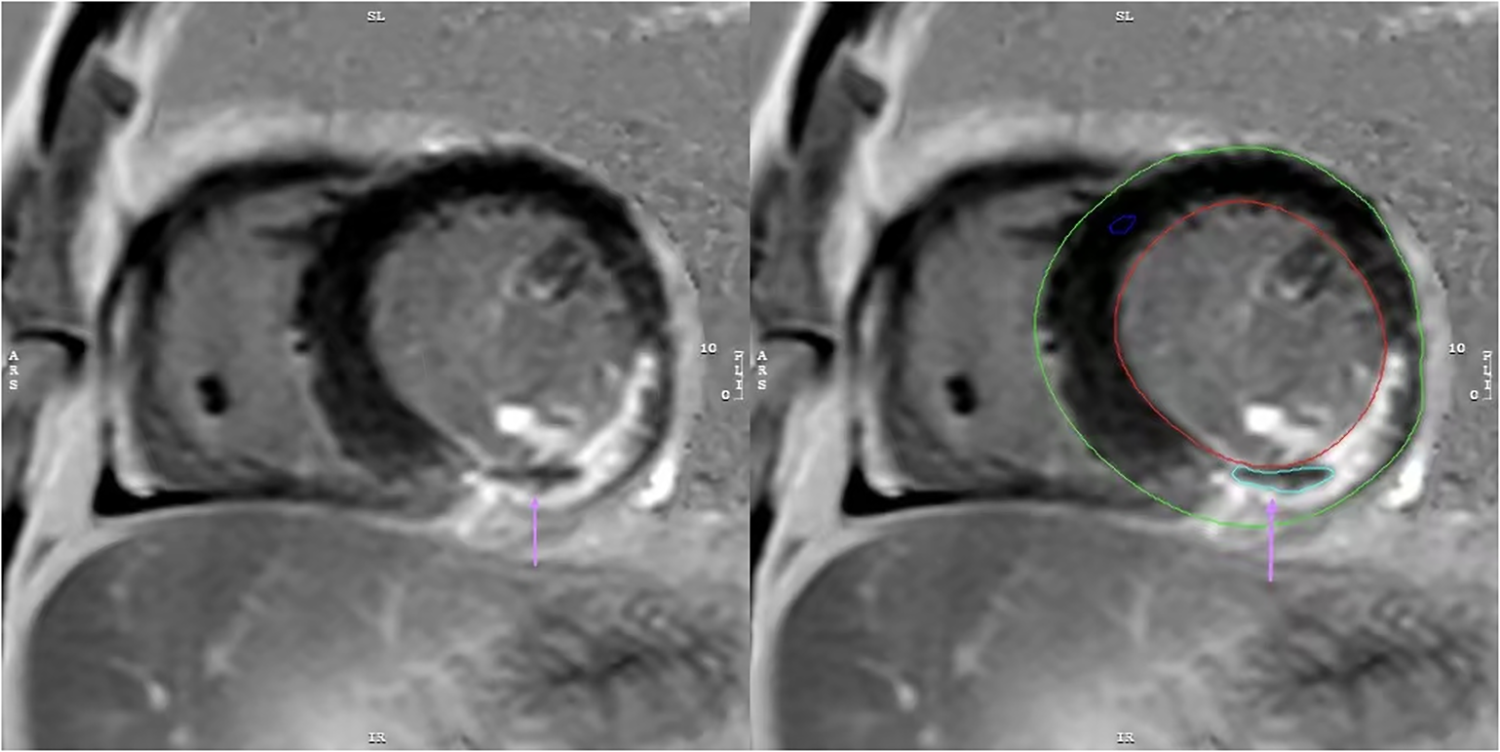

CMR and MVO image analysis: CMR images were acquired using a 3.0 T magnetic resonance scanner (Ingenia 3.0 T, Philips, Netherlands) during hospitalization, with a median timing of 5 days (interquartile range: 4–6 days). Images were acquired using the late gadolinium enhancement (LGE) sequence. Post-processing software (Cvi42, version 5.13.5, Circle V Vascular Imaging, Canada) was used to quantify cardiac parameters from CMR images. MVO was defined as low-signal areas surrounded by high-signal myocardial tissue in LGE images, and its mass was manually quantified relative to total myocardial mass (expressed as MVO%, Figure 2) (12). Similarly, LGE was defined as the myocardial infarct size percentage and was quantified as the ratio of hyper-enhanced myocardial mass relative to total myocardial mass (expressed as LGE%). A diagnosis of MVO was confirmed by experienced cardiovascular physicians, who were blind to related clinical data of patients to avoid bias, and all CMR data interpreted by them.

Figure 2

The image depicts a patient with myocardial infarction on the LGE sequence, manually outlined using CVI42 software. MVO is present as a region of low signal within the infarct area(↑).